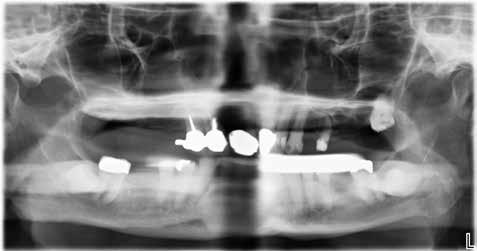

Fig. 1. Oversigt over udvælgelse af studiets kohorte.

Forkortelser: Antiresorptiv behandling (AR), Lavdosis antiresorptiv behandling (LDAR), Adjuverende antiresorptiv behandling (ADAR), Højdosis antiresorptiv behandling (HDAR), Medicinrelateret osteonekrose i kæberne (MRONJ).

Fig. 1. Overview of the study cohort selection.

Abbreviations: Antiresorptive therapy (AR), Low-dose antiresorptive therapy (LDAR), Adjuvant antiresorptive therapy (ADAR), High-dose antiresorptive therapy (HDAR), Drug-related osteonecrosis of the jaw (MRONJ).